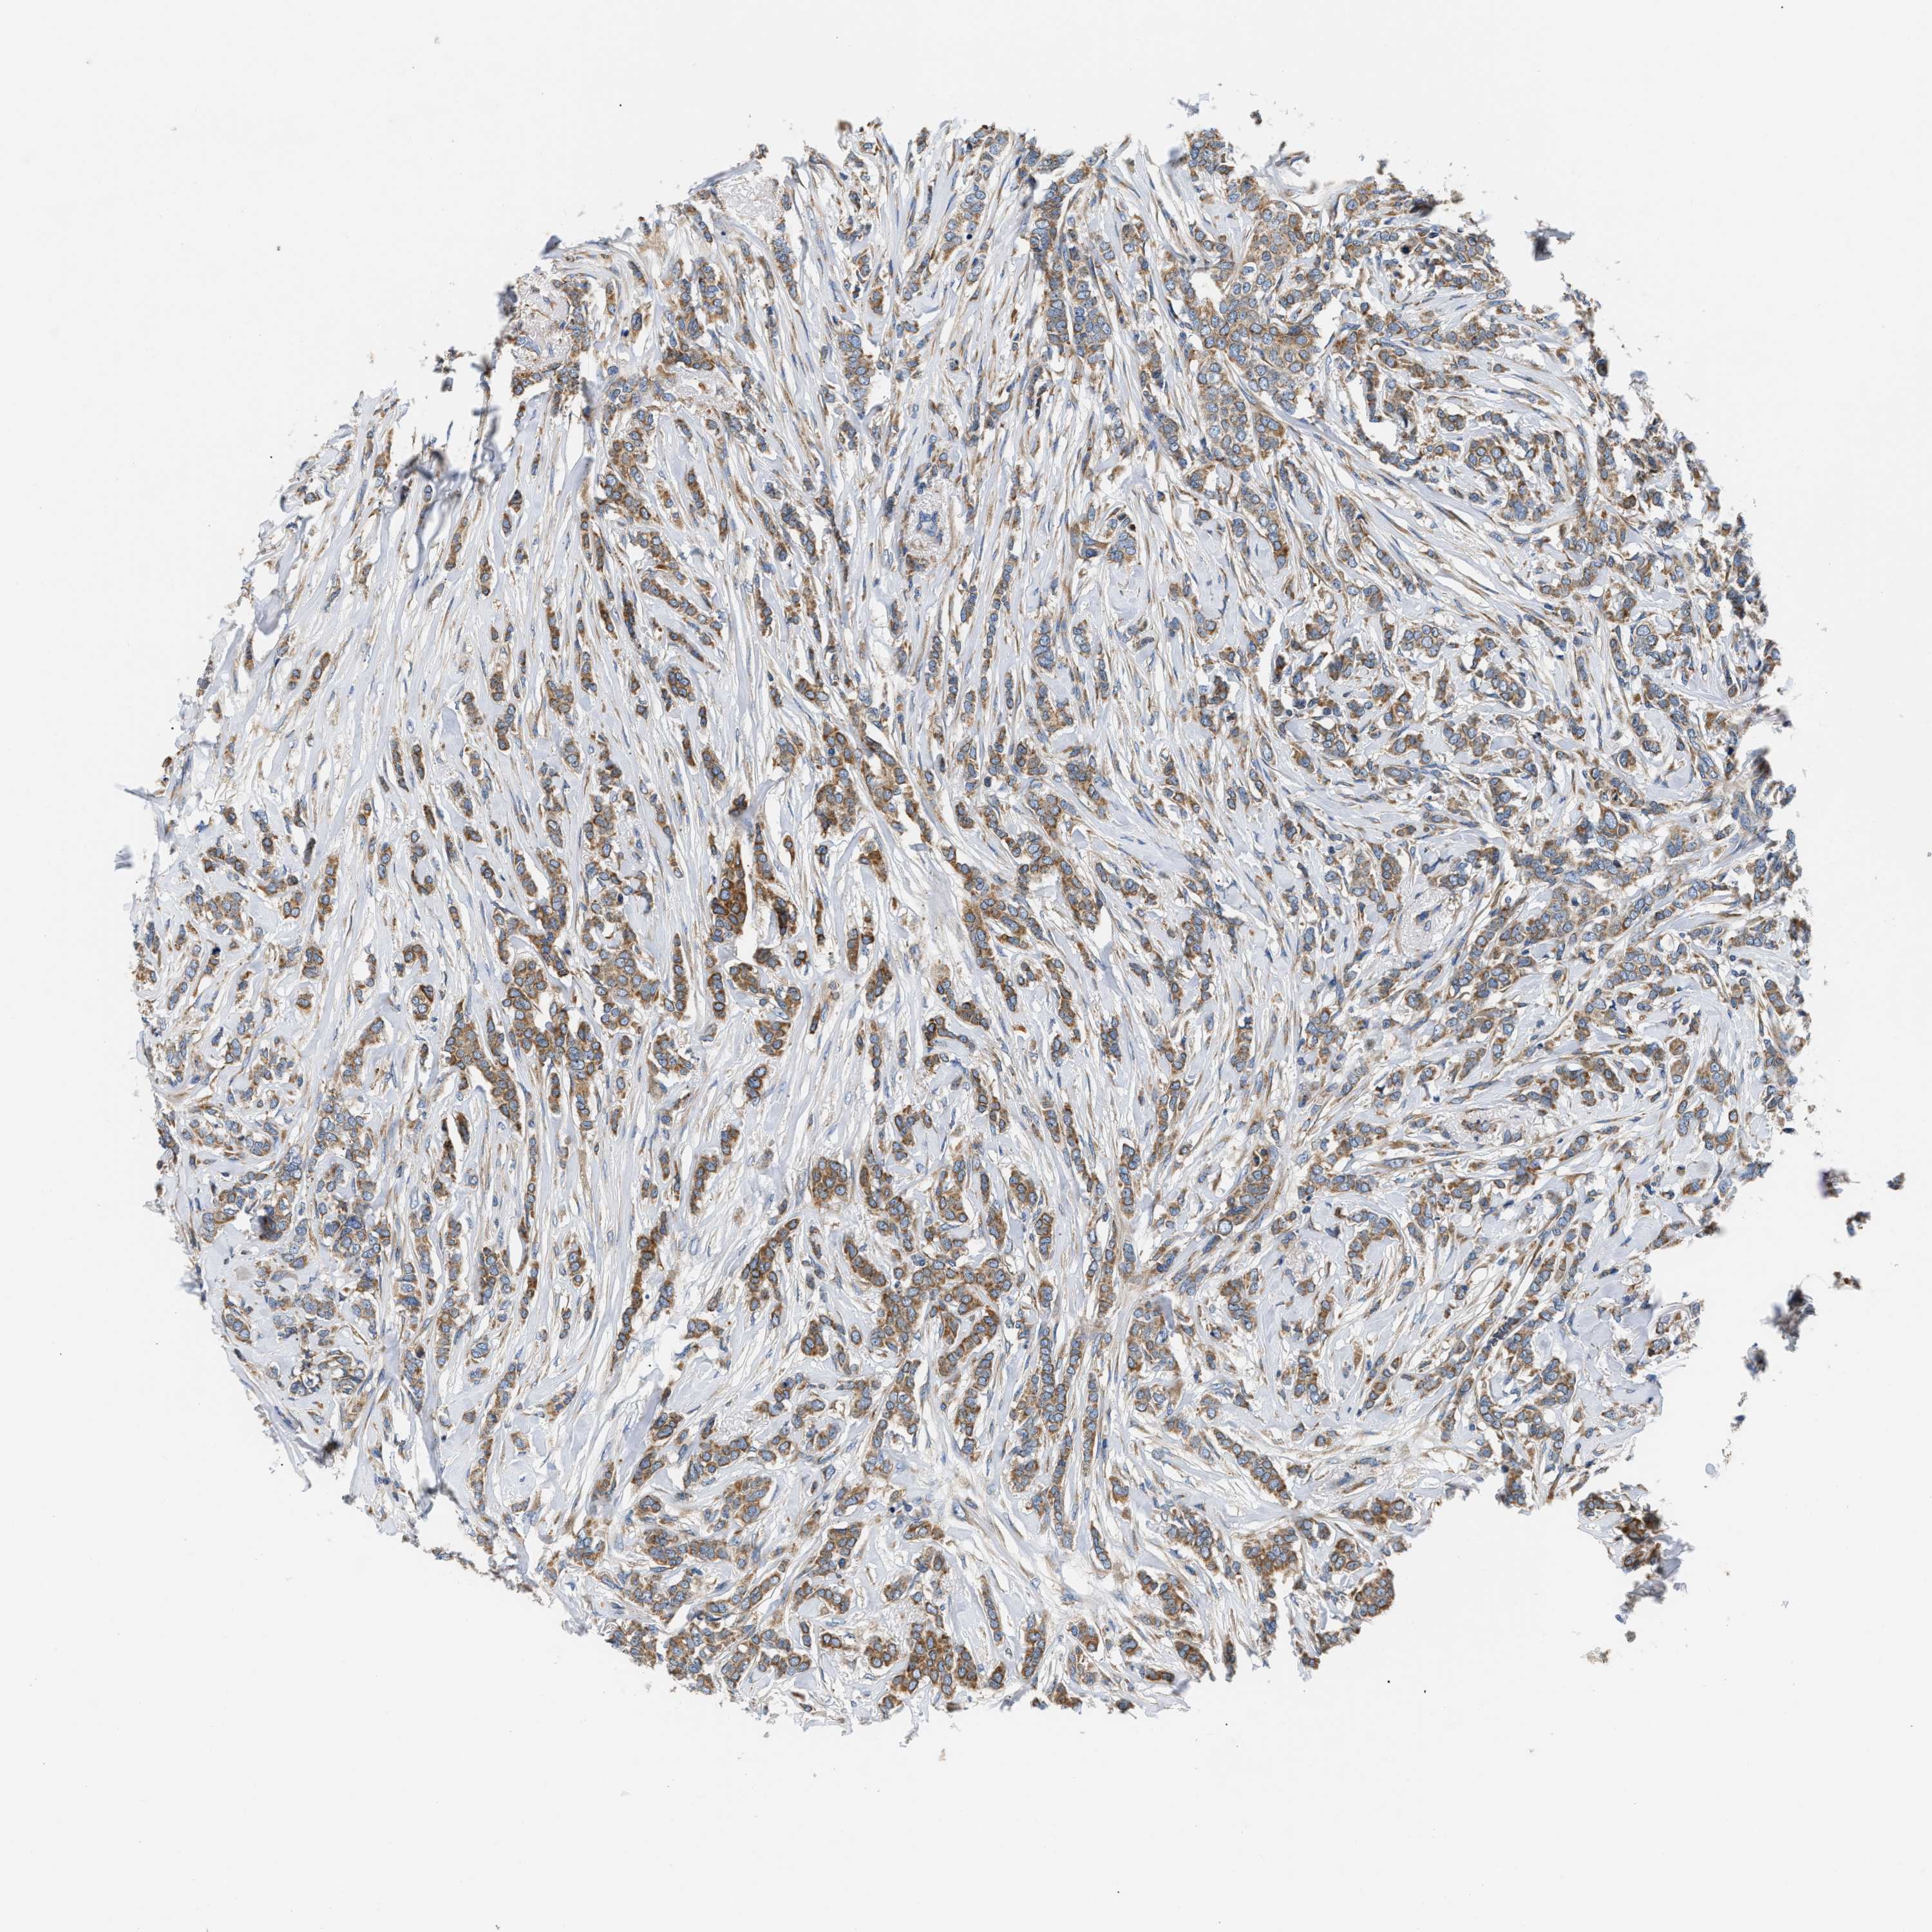

CANCER BREAST CANCER Show tissue menu

BRCA TCGA BRCA VALIDATION PROTEIN EXPRESSION